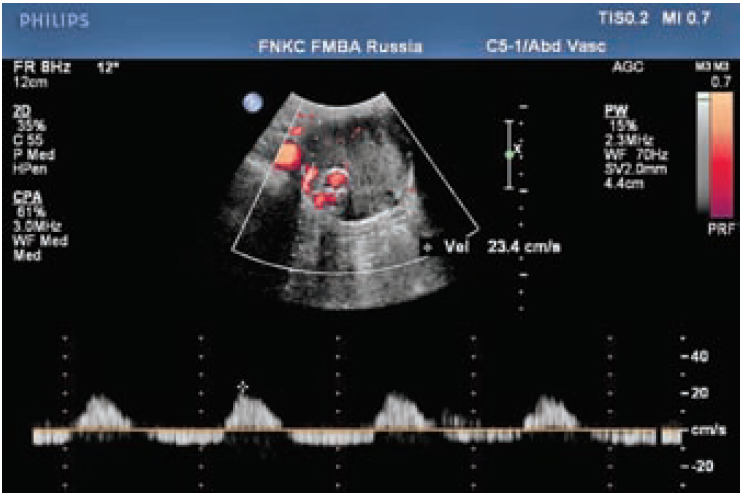

Рис. 3. Эндолик из поясничных артерий.

По данным КТ сосудов брюшной полости с КУ от 2017 года: Признаки эндолика из поясничной артерии

По данным ультразвукового исследования от 2017 года: Визуализируется аневризматический мешок диаметром 6,5 см. При картировании цветом уз-признаки эндолика 2 типа, кровоток в проекции задней стенки аневризматического мешка ЛСК-24 см/с (рис. 3).

Как видно из представленных клинических случаев, при помощи дуплексного сканирования возможно с высокой долей вероятности определить наличие такого осложнения как эндолик. Данные пациенты наблюдаются в динамике каждые 3 месяца.